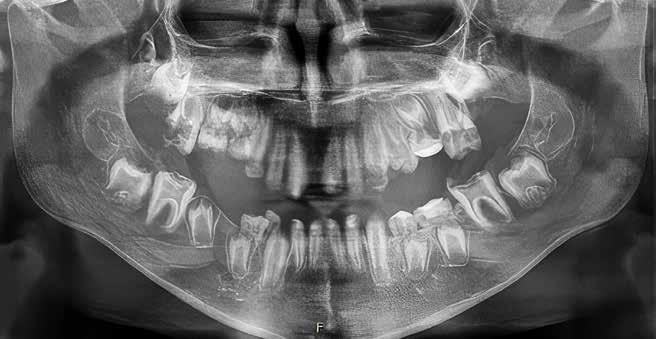

Udbyttet af disse nordiske fællesmøder kan vise sig i så konkrete tilfælde som et patienttilfælde med en udiagnosticeret otteårig pige, født med mitralklapinsufficiens, lav legemshøjde (-2 SD) og dysplastiske tænder med frembrudsproblemer og spontane nekroser til følge. Casen fremlægges på et møde, hvor to af deltagerne mener at have set lignende (Fig. 1A, B). Efter endt møde fremsendes yderligere information fra Aarhus med opfordring til, at der kunne være en mutation i LTBP3-genet, også

Panoramarøntgen 4 og 7 år

Fig. 1. A. 4-årig pige ved henvisning. Primære incisiver mistet på grund af spontane nekroser. Primære og permanente tænder ses dysplastiske og stort set uden emalje. B. Nu som 7-årig. 6’erne er endnu ikke frembrudt, men ses resorberede under slimhindedække. Der ses pulpaoverkapninger og endodontisk behandling af 1+, som har virket efter hensigten og bevaret tænderne i fronten. Endodontisk behandling på yderligere et antal tænder må forudses.

Fig. 1. A. 4-year-girl at the time of referral. Primary incisors have been lost because of spontaneous necrosis. Both permanent and primary dentition is without enamel and with dysplastic morphology. B. Same girl as 7-year-old. Molars are still not erupted but are seen to be resorbed preerupted. There has been done endodontic treatment in several teeth in the front, which has given function for now. It must be taken into account that more teeth will need endodontic treatment in the future.

kaldt DASS (Dental Anomaly and Short Stature). Efter yderligere henvisning til afdeling for klinisk genetik finder man en sygdomsfremkaldende variant i netop det gen (4). Pigen kan nu gå i relevant kardiologisk opfølgning og på sigt blive tilbudt relevant genetisk rådgivning og eventuelt prænatal diagnostik, når hun en dag selv ønsker at få børn. Ud over dette blev tandbehandlingen også drøftet i det nordiske forum. Patienten har siden tandfrembrud fået foretaget enkelte profylaktiske pulpaoverkapninger

og forseglinger af kronerne for at forebygge spontane nekroser. Dette gøres for at sikre tændernes bevarelse under væksten. På sigt forventes tænderne at mistes og erstattet implantatprotetisk, når dette findes relevant. Samtlige behandlinger er varetaget i højspecialiseret regi, men patienten følges også i primærsektoren, hvor samarbejdet mellem netop hospitalsbehandlingerne og kommunal tandpleje findes af stor betydning.